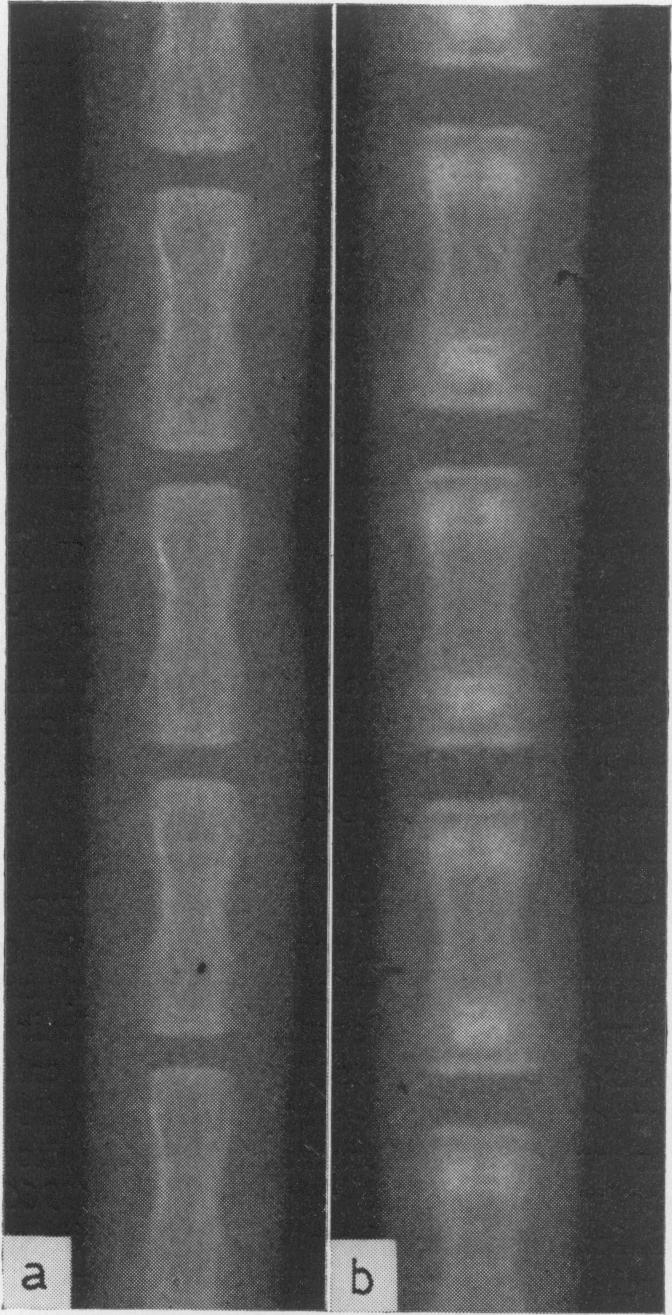

In 1962 Copp proposed the existence of a hypocalcaemic hormone. Subsequent studies have shown him to be right. Calcitonin is a potent inhibitor of bone resorption. By its action it lowers systemic blood calcium. It is secreted in response to hypercalcaemia by a distinct endocrine system within the thyroid in mammals and within the ultimobranchial bodies in fish, amphibia and reptiles. The active principle from pig has now been isolated and found to be a polypeptide composed of thirty-two amino acid residues. Together with parathyroid hormone, the hormone provides precise regulation of calcium concentration in the blood and controls bone remodelling and mineral turnover. Calcitonin in man may be secreted in excessive amounts by medullary carcinoma of the thyroid. In addition, aberrations in its secretion may play a role in pseudohyper-parathyroidism and ostepetrosis.

1962年,科珀提出存在一种降钙素。随后的研究证明他是正确的。降钙素是骨吸收的有效抑制剂。通过其作用,它可降低全身血钙水平。在哺乳动物中,它由甲状腺内一个独特的内分泌系统分泌以应对高钙血症;在鱼类、两栖动物和爬行动物中,则由后鳃体分泌。现已从猪体内分离出活性成分,发现它是一种由32个氨基酸残基组成的多肽。该激素与甲状旁腺激素一起,精确调节血液中的钙浓度,并控制骨重塑和矿物质代谢。人类的甲状腺髓样癌可能会分泌过量的降钙素。此外,其分泌异常可能在假性甲状旁腺功能亢进和骨石化症中起作用。